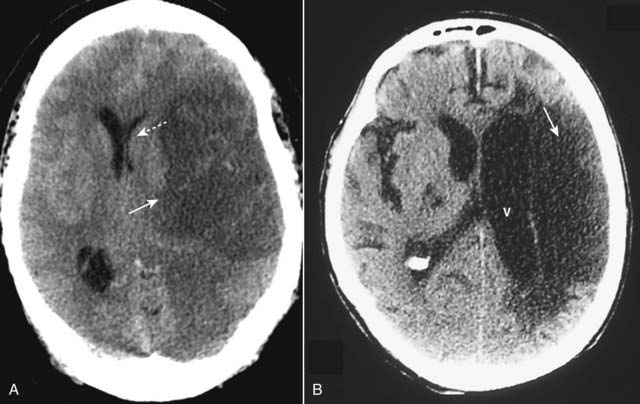

image

Figure 25-12 Brain herniations.

A, Subfalcine herniation occurs when the supratentorial brain, along with the lateral ventricle and septum pellucidum, herniate beneath the falx (solid white arrow) and shift across the midline toward the opposite side (dotted white arrow). B, Transtentorial herniation usually occurs when the cerebral hemispheres are displaced downward through the incisura beneath the tentorium compressing the ipsilateral temporal horn and causing dilatation of the contralateral temporal horn (solid white arrow). Both patients had large cerebral infarcts (I) with cytotoxic edema.

Figure 25-17 Ischemic stroke, newer and older.

The findings in ischemic stroke will depend on the amount of time that has elapsed since the original event. A, At about 24 hours, the lesion becomes relatively well circumscribed (solid white arrow) with mass effect evidenced by a shift of the ventricles (dotted white arrow) that peaks at 3 to 5 days and disappears by about 2 to 4 weeks. B, As the stroke matures, it loses its mass effect, tends to become an even more sharply marginated low attenuation lesion (solid white arrow), and may be associated with enlargement of the adjacent ventricle (V) due to loss of brain substance in the infarcted area.